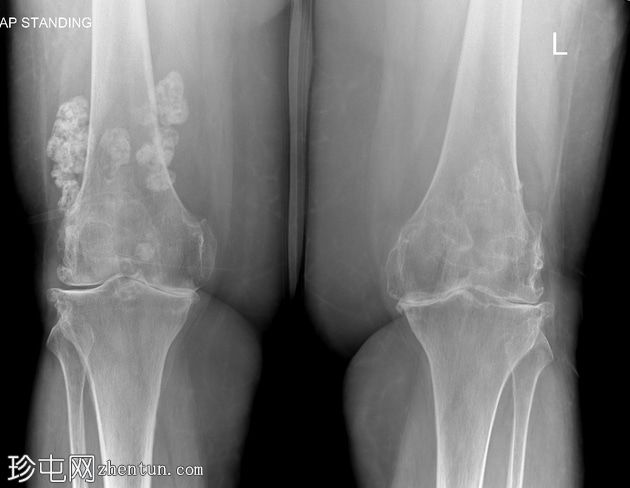

双膝X线片

X线片

正位片

侧位片

双侧胫股关节间隙明显变窄,伴软骨下硬化。

双侧髌股关节间隙变窄。双侧股骨和胫骨关节周围骨赘及髌骨骨赘。

右侧股骨远端软组织内可见多发致密钙化分叶状病变。未见骨折、骨膜反应或骨损伤。无内翻或外翻畸形。

本病例展示了继发性滑膜软骨瘤病伴严重膝骨关节炎的典型

影像

学表现。